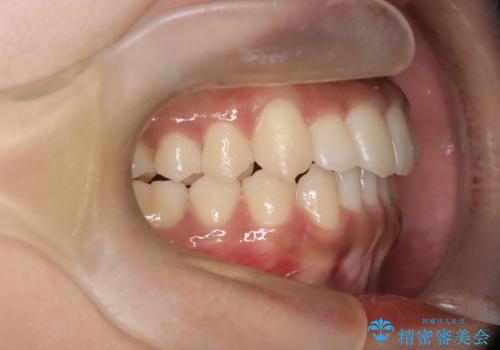

【インビザライン】笑ったときに目立つ八重歯をなおしたい

- 笑ったときに八重歯が見えることを主訴に来院されました。

下の前歯が一本足りない患者様でしたので、シミュレーションを作り、事前に患者様と治療ゴールのイメージをしっかり共有したうえでインビザラインを用いて治療を行っています。

奥歯を後ろのほうに動かすことで、前歯も少し下がることができ、矯正後の口元も満足していただきました。